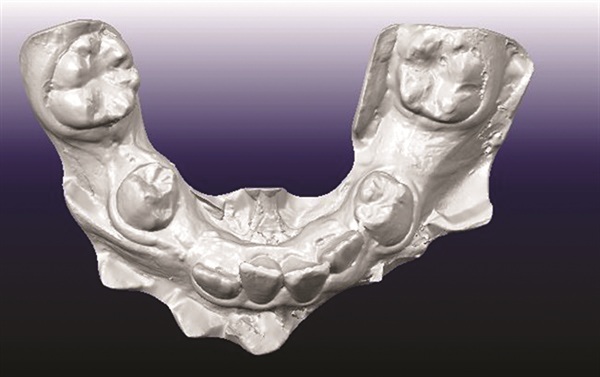

A 12-year-old male presented with severe Class II, deep bite, and significant crowding. The original poster was torn between two conflicting clinical pictures. Half the diagnostic findings pointed toward extraction: second molars impacted in the ramus, a blocked lower left canine, blocked maxillary canines, and a nearly full-step Class II relationship. The other half suggested non-extraction with vertical control to avoid deepening the bite further. The concern was that by the time crowding was resolved and the deep bite corrected, the incisors would be too flared for effective Class II correction without further proclination. The question posed to the forum was whether immediate upper first premolar and lower second premolar extractions were the best route forward (Figs. 1–11).

Before treatment planning could advance, multiple members flagged the need for better diagnostic records. The buccal photographs were not diagnostic, making it difficult to assess the true occlusal relationship. A severe transverse discrepancy was evident, along with possible soft tissue or skeletal asymmetry and potential maxillary cant. One clinician recommended obtaining a cone beam computed tomography scan to properly evaluate the asymmetry before finalizing any treatment plan. Another emphasized the importance of retraining staff on proper photo protocols to avoid similar issues in future cases. The original poster acknowledged the feedback and posted updated images.

Once better records were available, opinion shifted strongly toward rapid palatal expansion as a necessary first step. Several contributors noted the obvious transverse deficiency and recommended expansion before making final decisions about which teeth to extract. Some leaned toward extracting second premolars even in a Class II case, while others preferred a non-extraction approach if feasible.